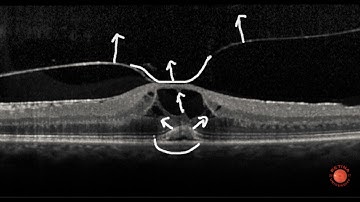

OCT scan of the retina